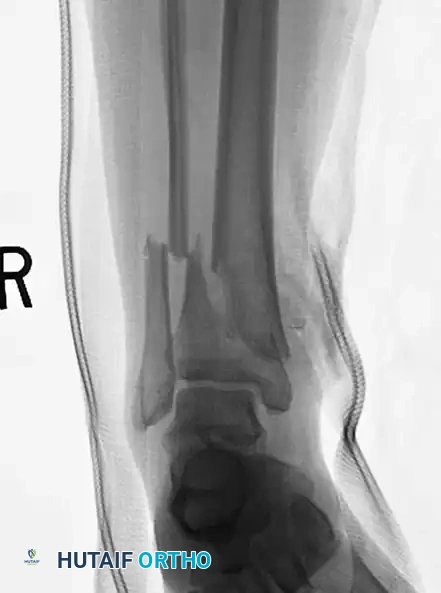

Locked intramedullary (IM) nailing is universally recognized as the gold standard and treatment of choice for the vast majority of type I, type II, and type IIIA open, as well as closed, tibial shaft fractures.

IM nailing offers superior biomechanical advantages by acting as a load-sharing device positioned at the mechanical axis of the bone. This minimizes bending moments compared to eccentrically placed plates. Furthermore, IM nailing preserves the critical soft tissue sleeve and periosteal blood supply around the fracture site, promoting secondary bone healing via callus formation and allowing for early mobilization of adjacent joints.

The ability to lock the nails proximally and distally provides absolute control over length, alignment, and rotation in unstable, comminuted, or segmental fractures. Modern interlocking designs permit the stabilization of fractures located as far proximal as the tibial tubercle or as far distal as 3 to 4 cm proximal to the ankle joint plafond.